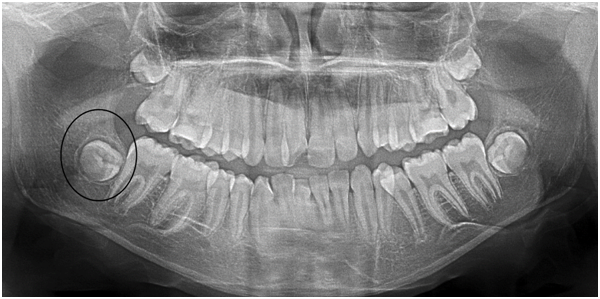

In order to achieve higher accuracy in defining the stages of development towards apexification, the Demirjian method was modified and two stages were added, F1 and G1, making ten stages of the crown and root formation (Figure 1).16

Figure 1 Schematic drawings and definitions of the ten stages of crown and root formation used to score third molar development and Modified Demirjian method was adapted to the Turkish population.

Figure 3 The right third mandibular molars were evaluated with panoramic radiographs. (15 years male-Stage D).

The modified Demirjian stages of tooth development9,16 used in this study were designed for third molars. Third molar formation stages were rated because of the absence of other reliable biological markers during late adolescence. Solari et al.16 analyzed the stage of third molar development using the eight-grade scheme developed by Demirjian and coworkers and described that In Hispanics, the mean ages at each developmental stage were lower for males than for females. Results of the present study agree with a previous one, the mean ages at A, C, D, E, F1, G, G1 developmental stage were lower for males than for females and B and F were lower for females than males (Table 2). This result is confirmed by Zhai,8 Gungor,13 Solari,16 Mincer et al.20 Compared with the present study and similar results are seen in the mean ages of the third molar at given stages of tooth development. However, it is observed at all groups that crown-root formation earlier completed in the Turkish children and young adults.

In the present study, F stage and F1 stage are similar age ranges (Figure 1‒3).There is a proportional increase in other value ranges, where similar values are seen here suggest that F runs for a shorter time or that F and F1 are confused during the examination.